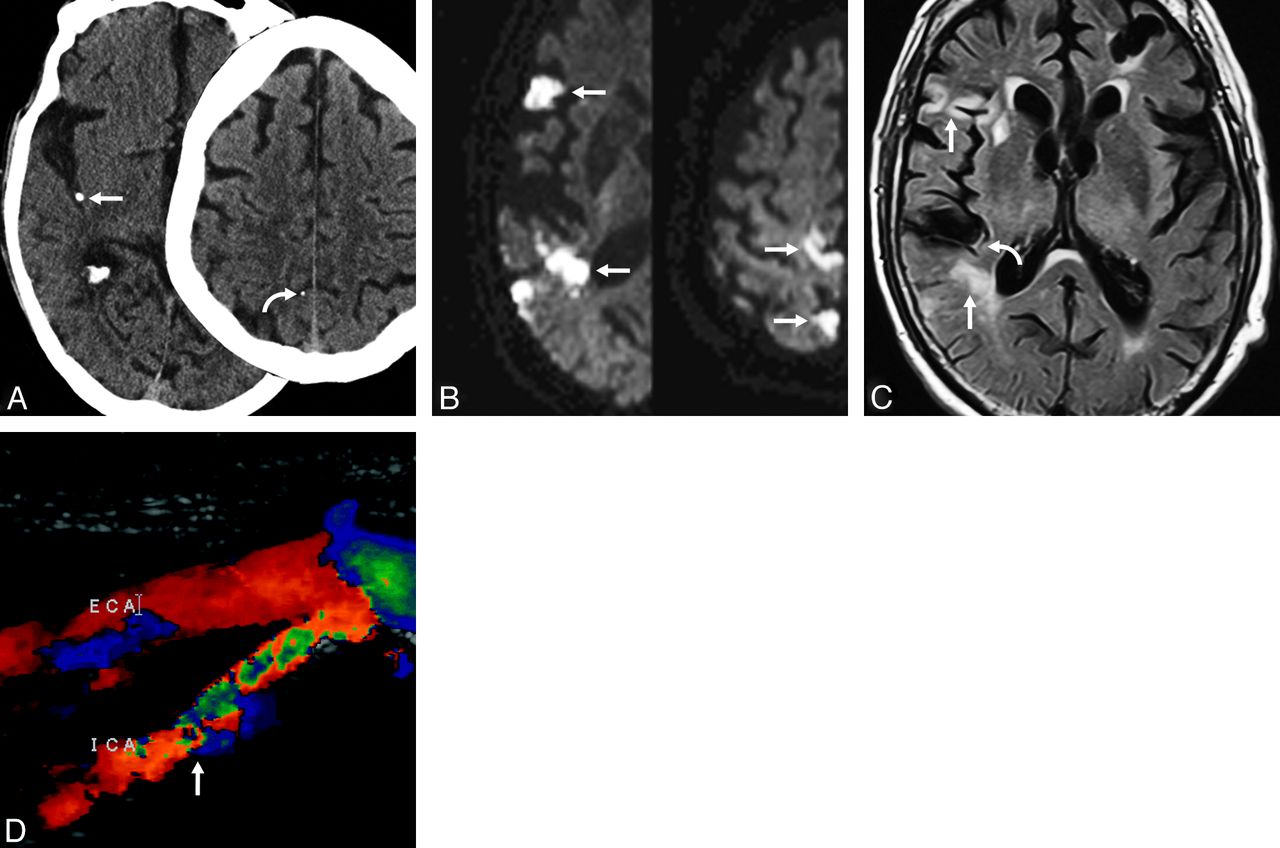

Case 3. Axial nonenhanced CT of the head (A) in an 89-year-old man presenting with acute onset of left hemiparesis. A hyperattenuated focus (straight arrow) measuring 345 HU, consistent with calcified embolus, is seen within the posterior distribution of the right MCA. A second embolus is seen more superiorly (curved arrow). Axial diffusion tensor imaging (B) of the same patient reveals diffusion restriction within multiple areas (arrows) in the right MCA distribution, including both the anterior and posterior divisions, indicating multiple cortical infarctions. These infarctions are likely the result of noncalcified emboli dislodged from the same location as the calcified embolus. FLAIR (C) reveals multiple areas of FLAIR hyperintensity (straight arrows) in the same areas as the restricted diffusion, consistent with late acute-to-subacute infarction. There is also intravascular hyperintense signal showing slow flow (curved arrow) distal to the calcified embolus. Sonography (D) shows stenosis of the right internal carotid artery (arrow) as the likely source of emboli. Initially, the large calcified embolus (A, left) was diagnosed as a calcified vessel wall. A smaller second embolus (A, right) was overlooked as was a third calcified embolus (not shown).